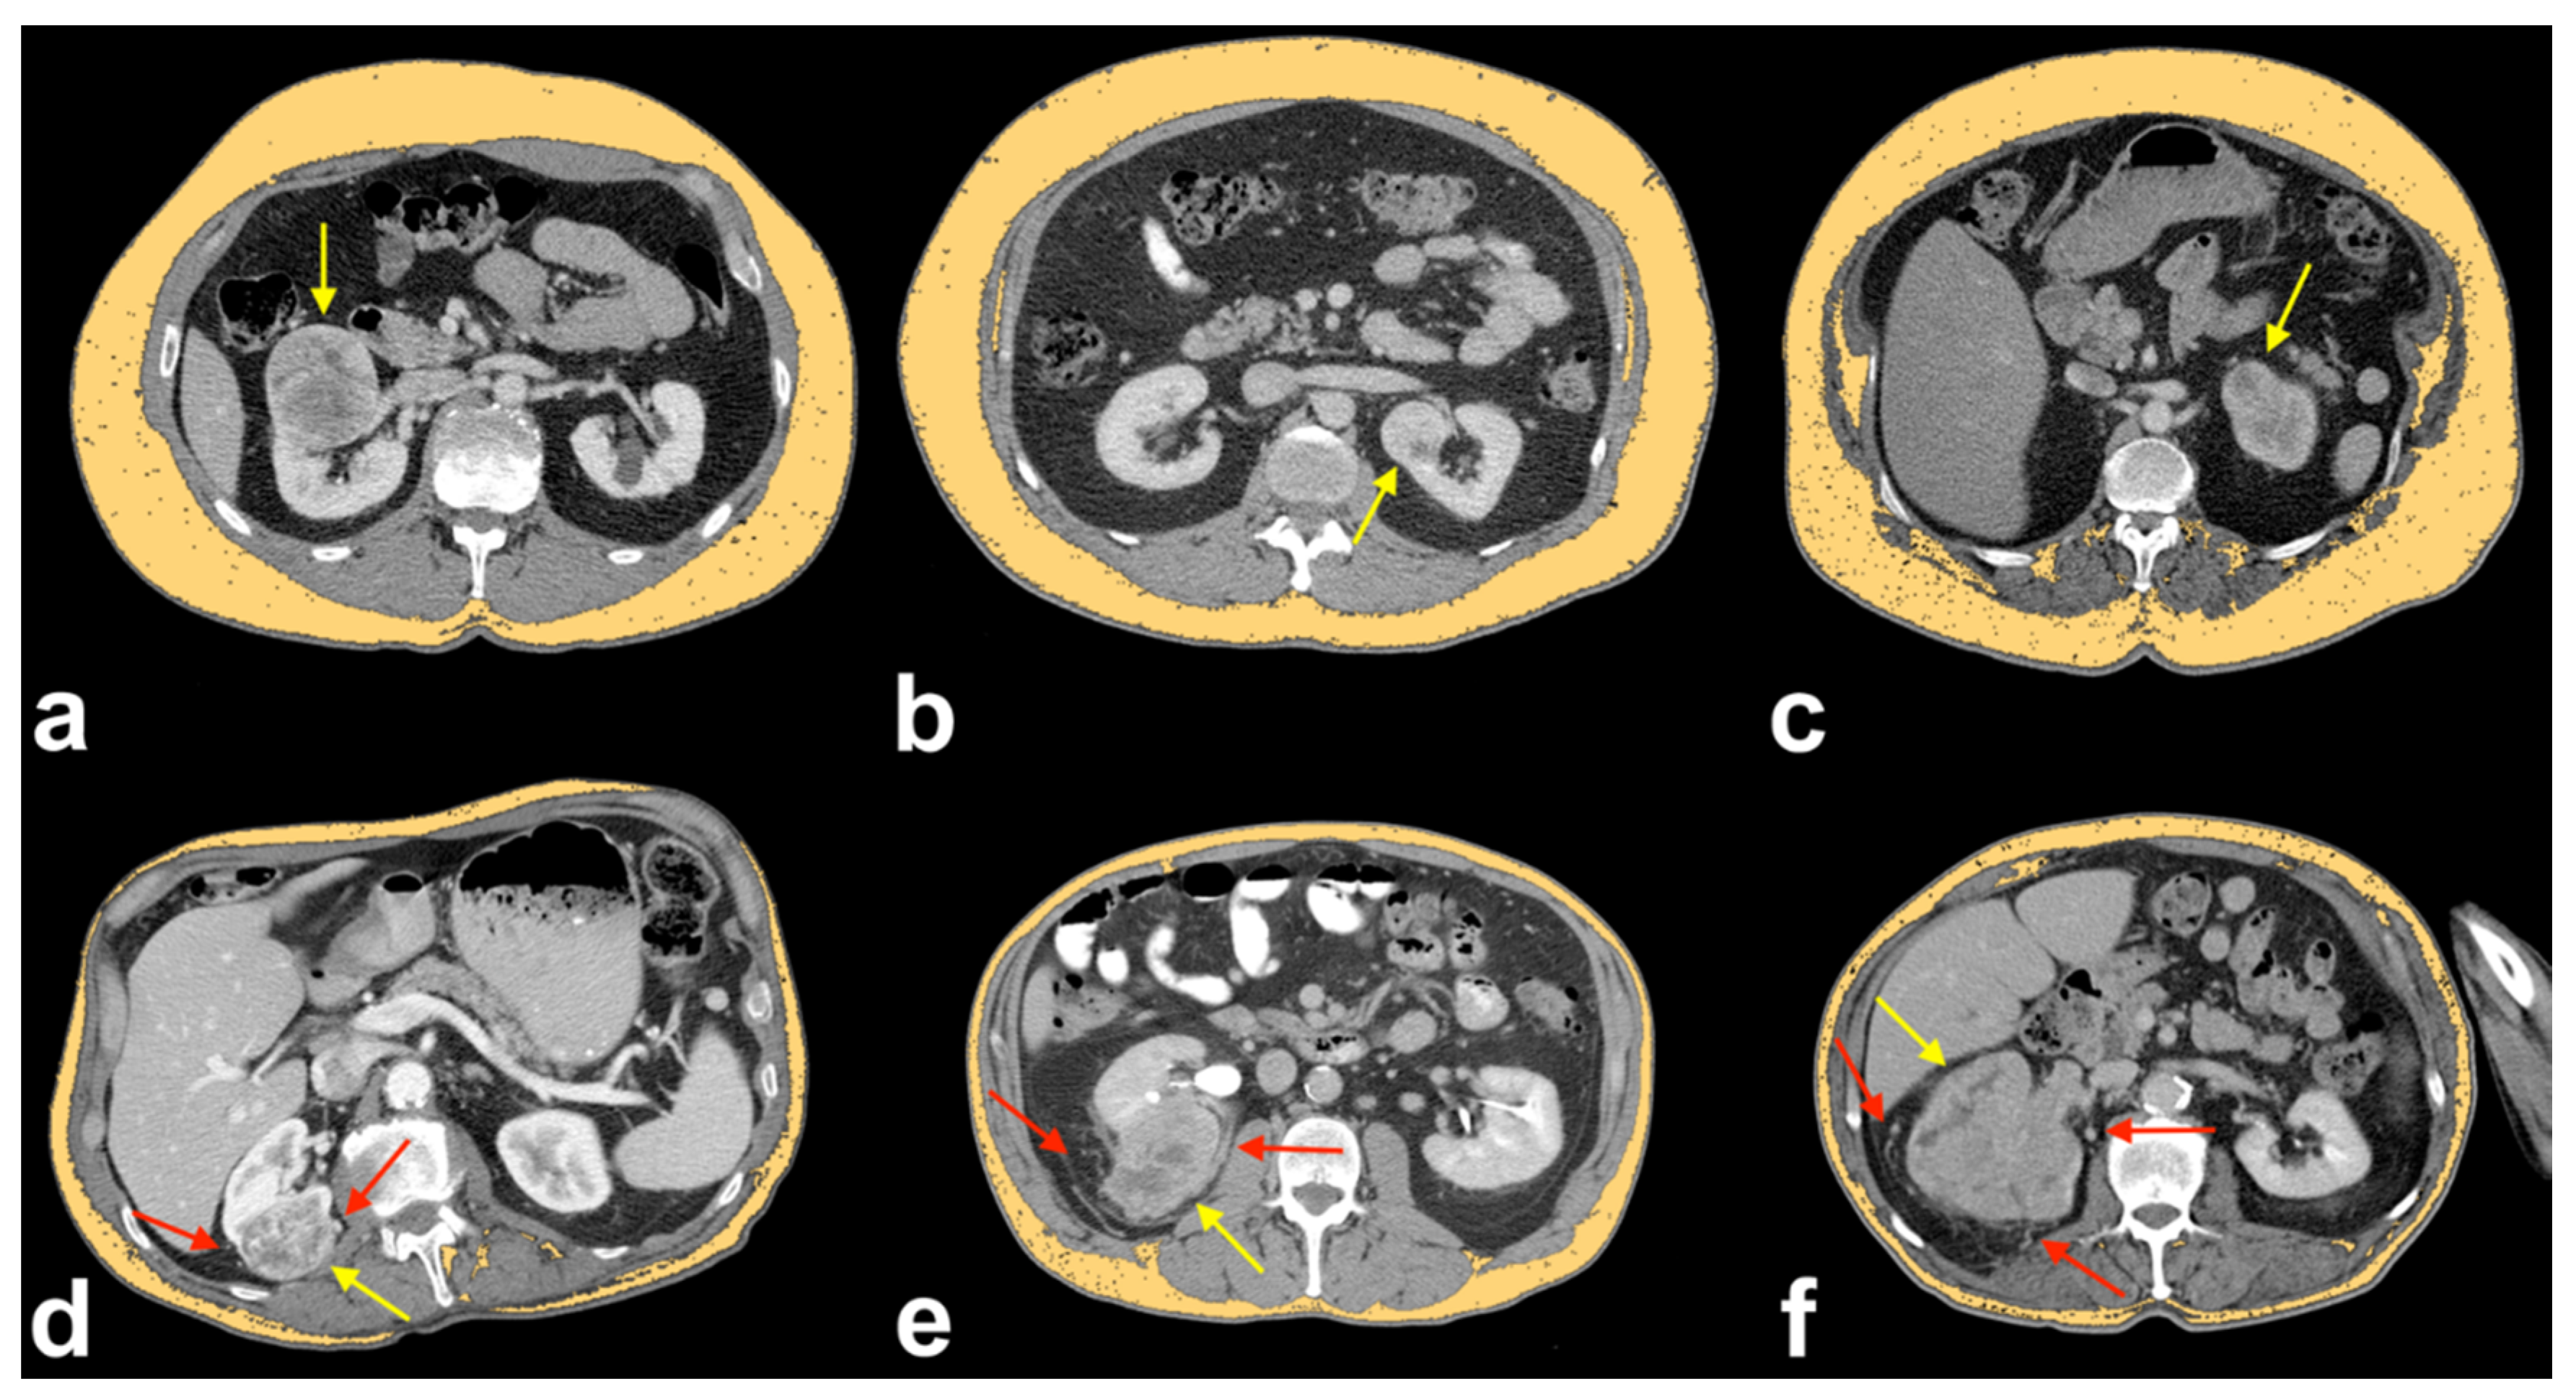

All patients underwent CT examination. For the evaluation of collateral vessels and quantification of adipose tissue we used CT images obtained after intravenous administration of an iodine-based contrast medium. Horos v.4.0.0 RC2 software was used for the quantification of TAT, VAT and SAT, by means of a semi-automatic function that allowed us to detect the attenuation values of adipose tissue (i.e., about −100 Hounsfield Unit). The slice chosen for the measurements of areas (cm2) was located 3 cm above the lower margin of L3, according to a previously described technique (Figure 2) [18]. All the regions of interest (ROIs) were drawn by consensus of two radiologists (F.G., 5 years of experience; C.A.M., 9 years of experience), blinded to clinical data.

Figure 2.

Axial CT images showing a single slice located 3 cm above the lower margin of L3 without ROIs (a) and the same slice with superimposed colored ROIs of VAT area (red ROI) and of SAT area (cyan ROI) (b). The sagittal plane, depicted in the middle, has been used as a reference to drive the correct ROI drawing for each subject.